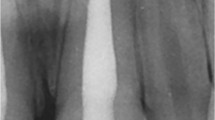

Patients over the age of 16 with radiographic evidence of apical periodontitis and a diagnosis of pulpal necrosis confirmed by negative response to hot and cold tests were randomised to receive either a one or two visit root canal treatment (RoCT).

Two hundred and eighty-seven patients (300 teeth) were randomised. One hundred and fifty-five teeth were allocated to the single visit group and 145 to two-visit treatment. Eighteen teeth were lost to follow up, nine from each group. At two years there were no significant differences between the groups, with 96.57% (141 of 146 teeth) in the single-visit group being classified as healed compared with 88.97% (121 of 136 teeth) in the two-visit group.

This study provided evidence that a meticulously instrumented single-visit root canal treatment can be as successful as a two-visit treatment. There was no significant difference in radiographic evidence of periapical healing between single-visit and two-visit root canal treatment.